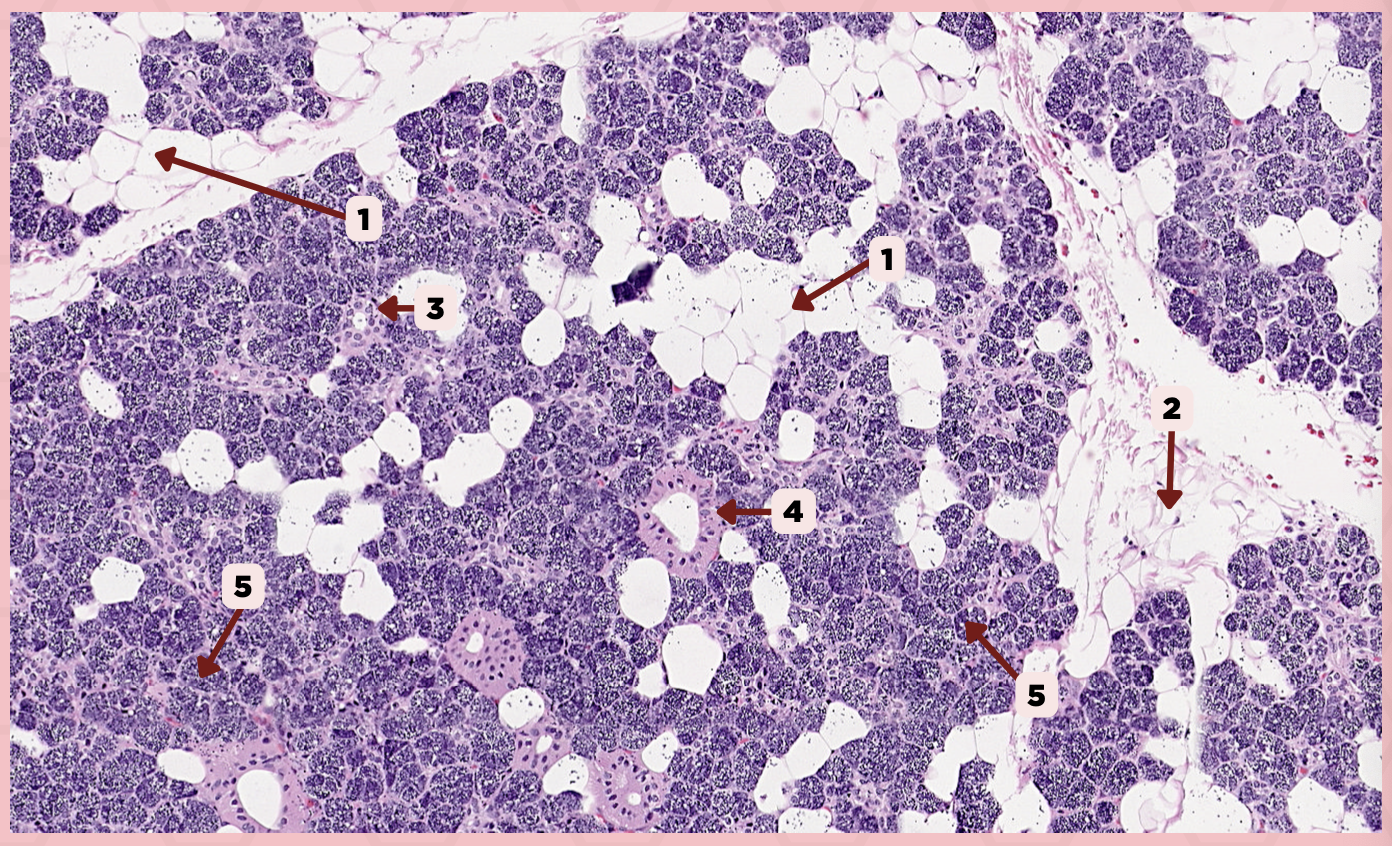

Parotid

Identify the specimen.

Capsule

Identify the structure labeled as 1.

Lobule

Identify the structure labeled as 2.

Lobe

Identify the structure labeled as 3.

Connective Tissue

Identify the structure labeled as 4.